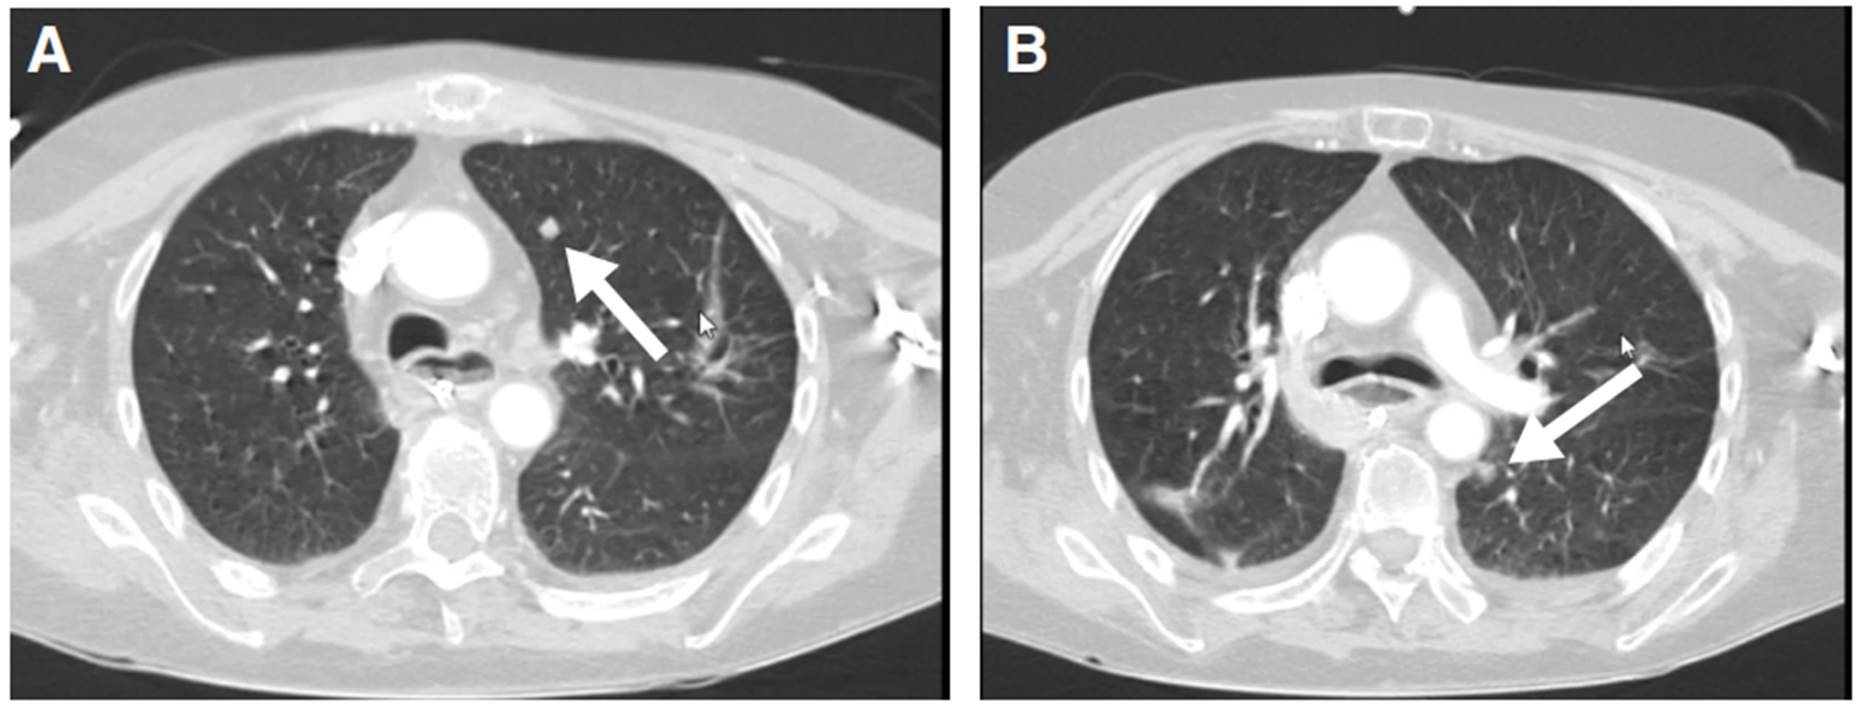

Figura 2 A. Nódulo con densidad de tejidos blandos en el lóbulo superior del pulmón izquierdo. B. Nódulo con densidad de tejidos blandos en el lóbulo inferior del pulmón izquierdo

En la segunda TC de cráneo se encontró hidrocefalia no comunicante (figura 1). En la punción lumbar, se obtuvo un líquido raquídeo de aspecto turbio, cuya viscosidad no permitió medir la presión de apertura; las proteínas estaban en 1.000 mg/dl, los leucocitos en 2 por mm3, la glucosa en 33 mg/dl y el antígeno de Cryptococcus dio positivo. En el cultivo del líquido cefalorraquídeo, se detectó C. neoformans. Además, una tomografía de tórax de alta resolución demostró compromiso nodular multilobar (figura 2).